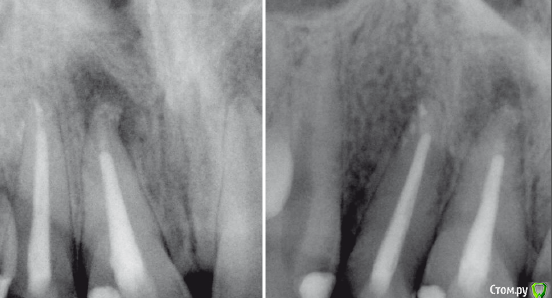

Slaggy Опубликовано 21 декабря, 2015 Поделиться Опубликовано 21 декабря, 2015 Было 06/2015 2 недели - кальций, Апекс- триоксидент, дальше латералка Акросил.Стало 12/2015 Жалоб не предъявляет.Сделать резекцию или пусть живет? Ссылка на комментарий

Fibez Опубликовано 21 декабря, 2015 Поделиться Опубликовано 21 декабря, 2015 Ждите еще полгода. Если не покатит- резекция с ретроградкой. На одном, вроде, улучшение видно. Ссылка на комментарий

Ker Опубликовано 21 декабря, 2015 Поделиться Опубликовано 21 декабря, 2015 имхо - не трогать пока.на обоих стало лучше.если не станет, то перелечить попробовать еще раз. Ссылка на комментарий

Чертков Александр Опубликовано 22 декабря, 2015 Поделиться Опубликовано 22 декабря, 2015 Видно же явные улучшения! Подождите! ...а то нетерпиться за нож схватиться... Ссылка на комментарий

Гарриевич Опубликовано 3 января, 2016 Поделиться Опубликовано 3 января, 2016 Было 06/2015 2 недели - кальций, Апекс- триоксидент, дальше латералка Акросил.Стало 12/2015 Жалоб не предъявляет.Сделать резекцию или пусть живет?Коллега, 6 месяцев это только первый пик заживления, на нем может вообще не быть улучшения или оно может быть незначительным. По совести окончательное решение healing/healed/fail принимается спустя 4! года. Но даже если никакой, ни положительной, ни отрицательной динамики не будет, но при этом зуб будет бессимптомный, то он признается "functional" и живет спокойно без никаких резекций 4 Ссылка на комментарий